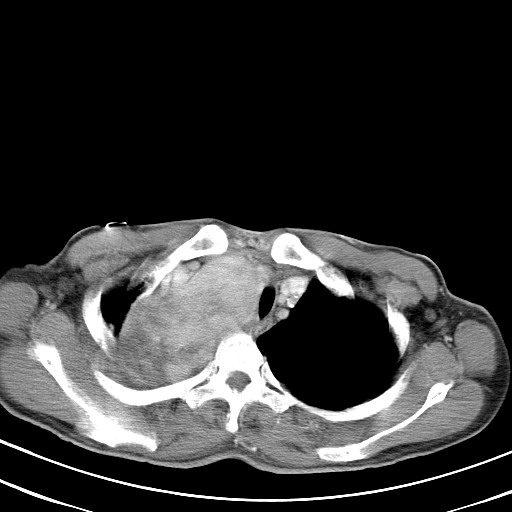

以下是引用汪涛同志在2007-8-2 0:40:00的发言:[br]病变虽然广泛,同时侵及双侧纵隔,但是无论左侧和右侧上下观察都是与右侧颈部甲状腺相延续的,而且强化幅度基本一致,又同时具有恶性病变病变的某些特征:肿块过大且密度不均,部分层面与正常纵隔结构分界不清,结合病史已有两年,考虑:胸内甲状腺肿恶变可能。[br]